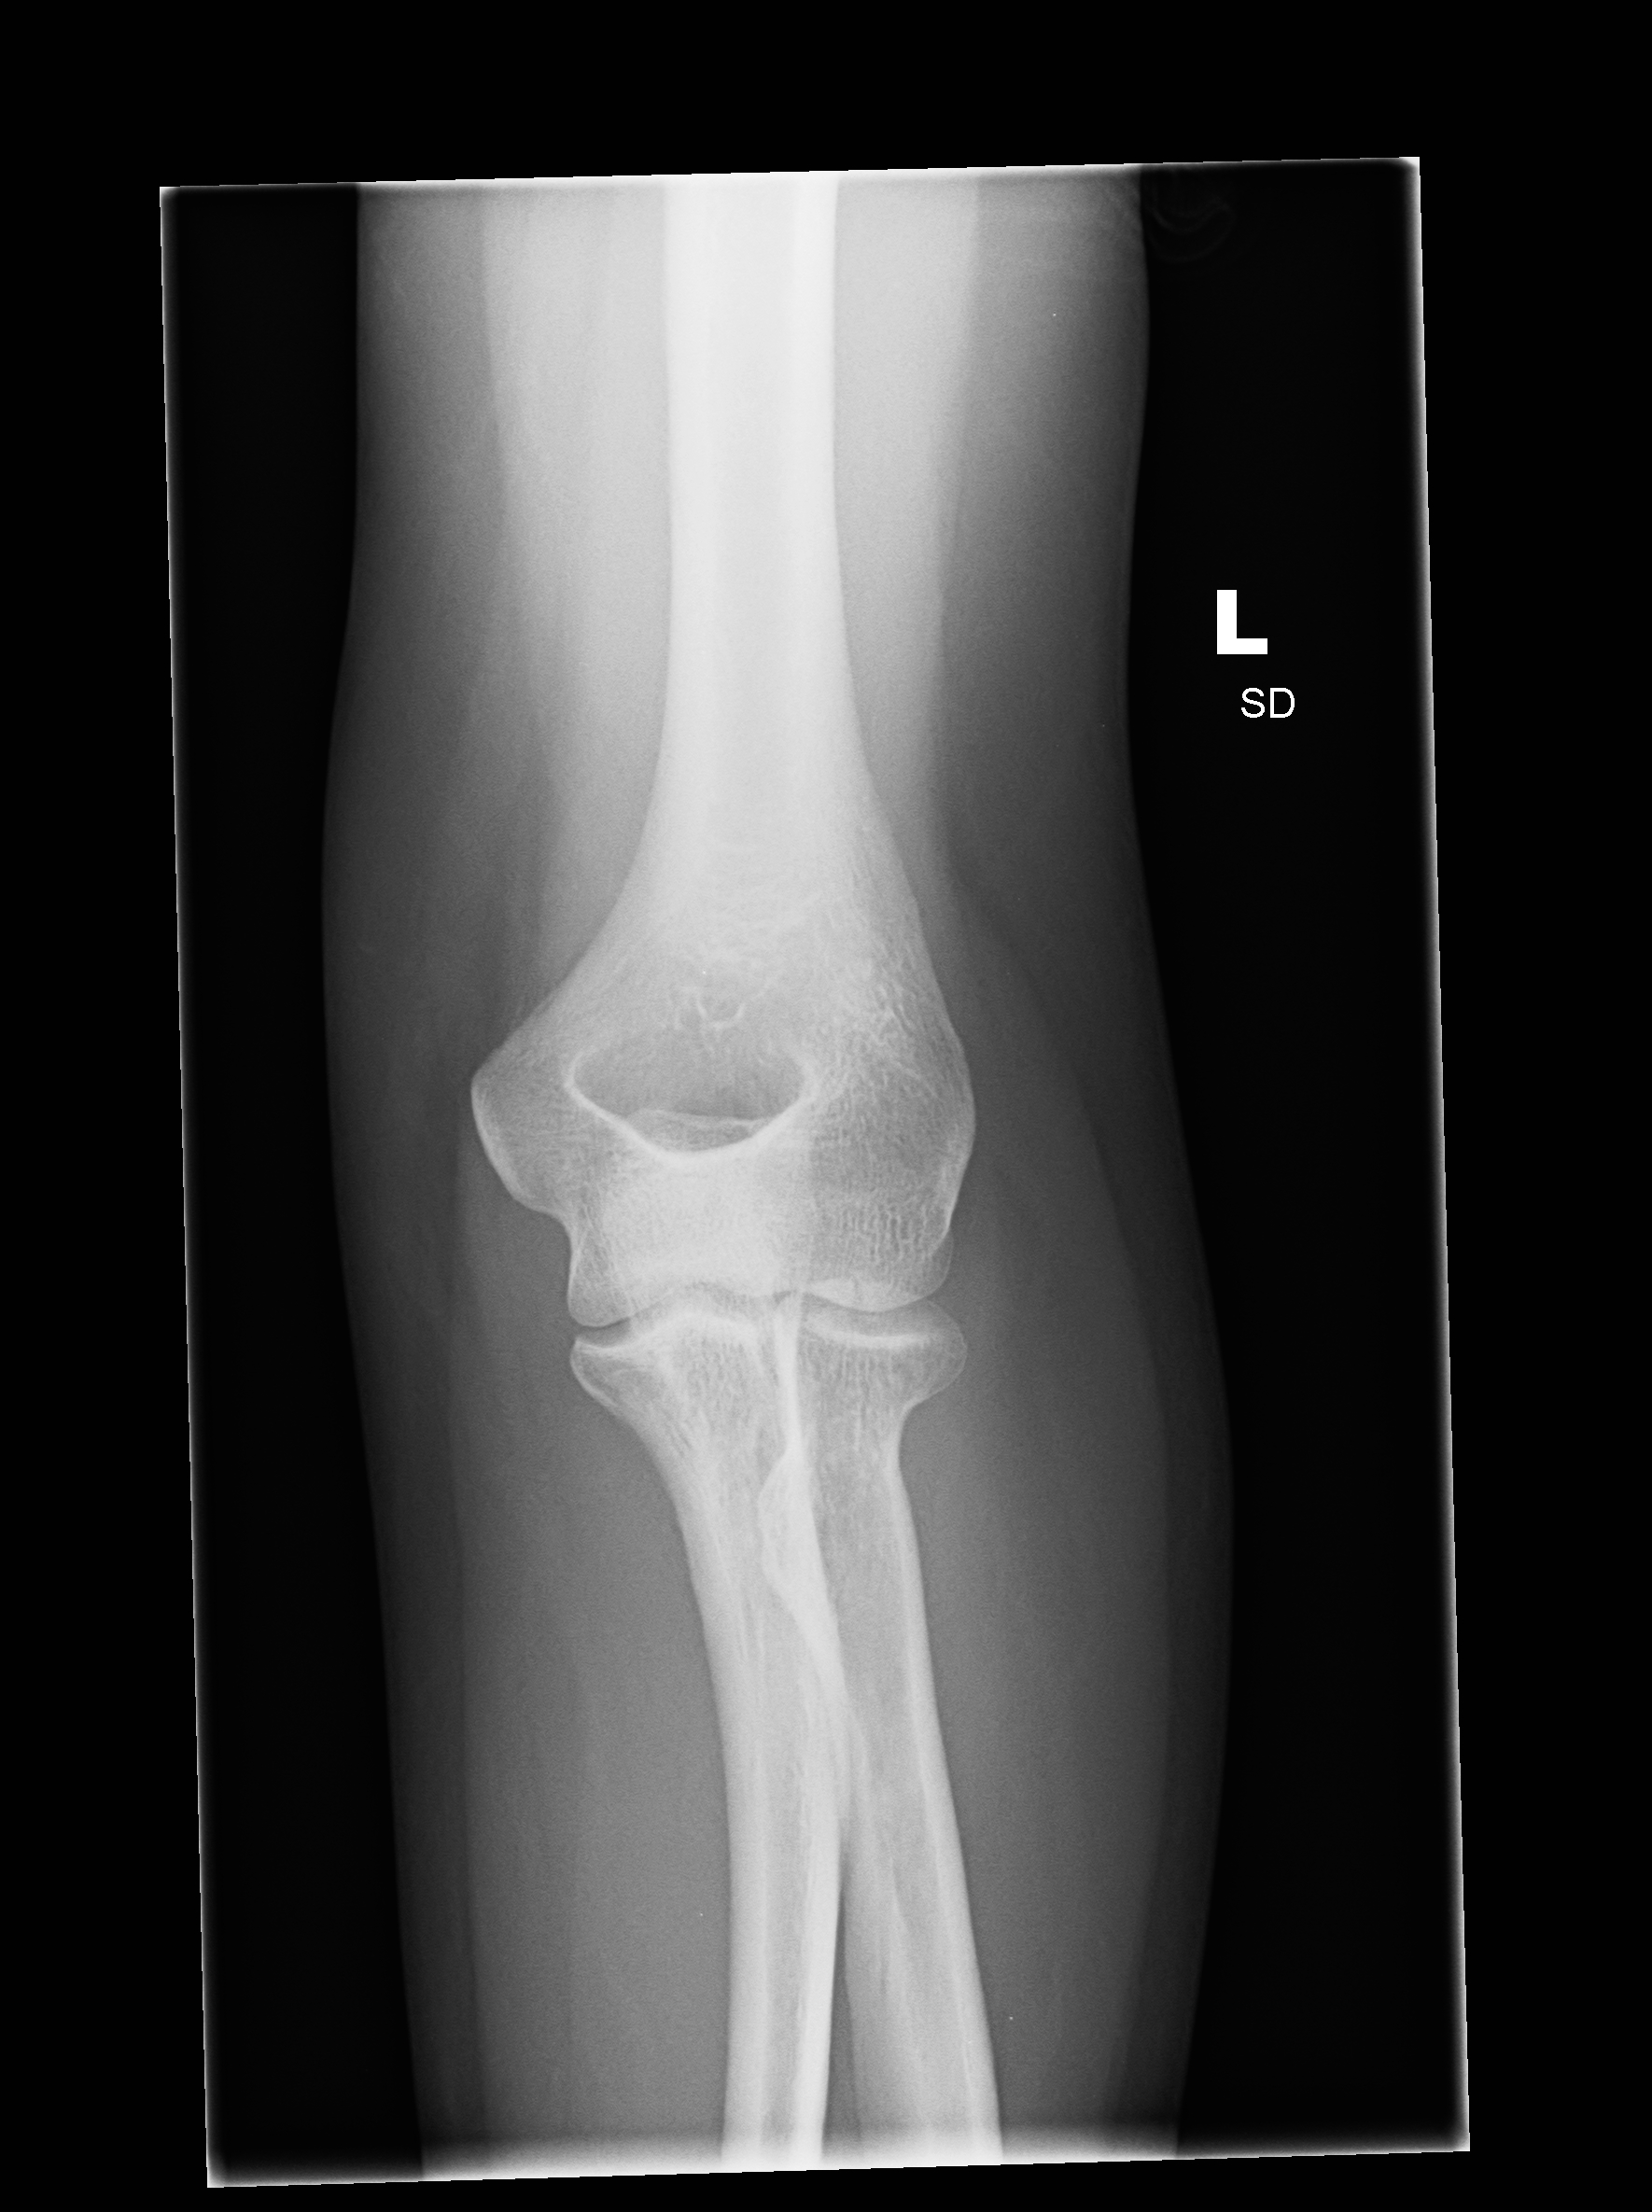

| 3 |

Abnormal fr rad head |

Abnormal Left radial head fracture |

Correct |